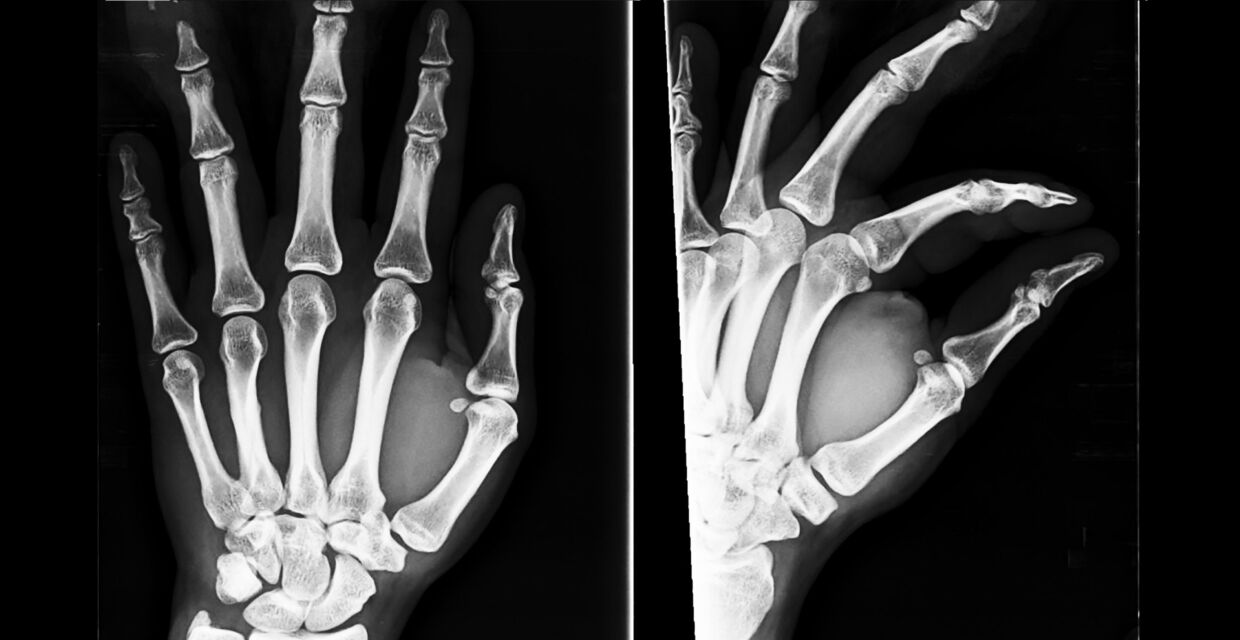

Scaphoid fractures can be difficult to identify as they do not usually cause significant swelling or bruising. If a fracture is suspected then an x-ray should be requested.

If the x-ray is clear but the clinical picture suggests a fracture, then medical professionals should manage the patient as having a suspected fracture. Delaying the diagnosis of a scaphoid fracture can cause the wrist to develop long term problems.